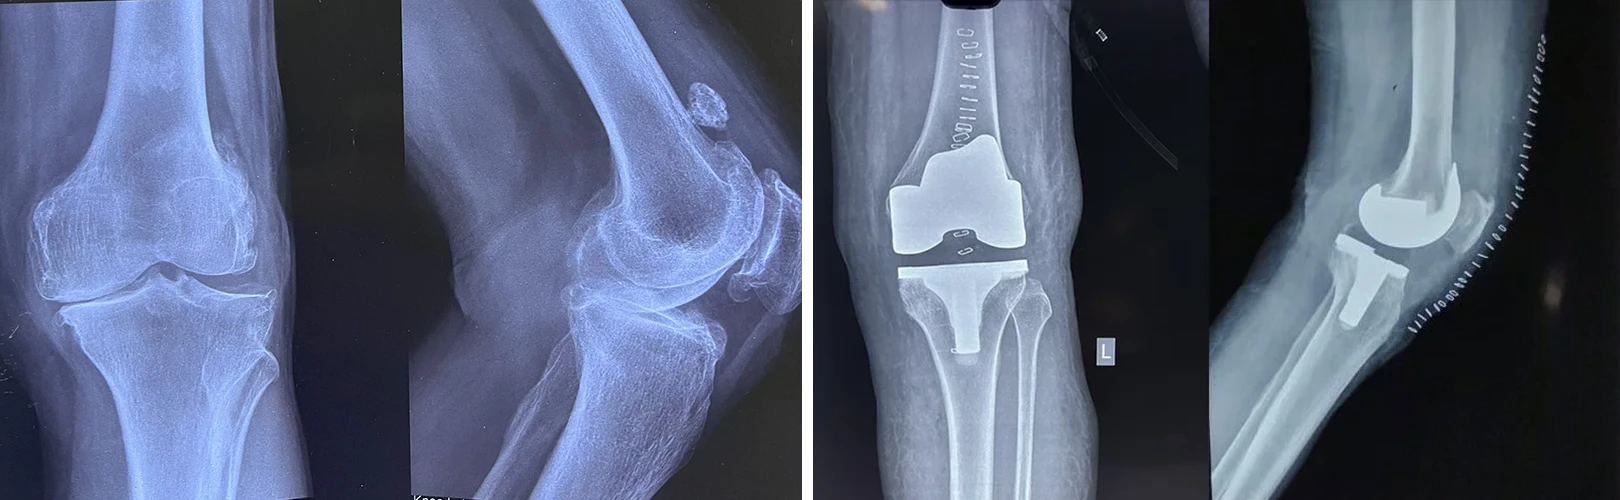

Total Hip & Knee Arthroplasty

During his two year Post Doctoral Programme , he attained rigorous & specialised training in Arthroplasty, focusing on Primary, Complex Primary, Revision & Robotic Total Hip and Knee replacement.

Total Knee Replacement

Are you having pain in your knees? Look no further, because Dr. Sanyal is the best choice for you. He specialises in total knee replacement surgery, offering you a solution to regain your mobility and live pain-free.